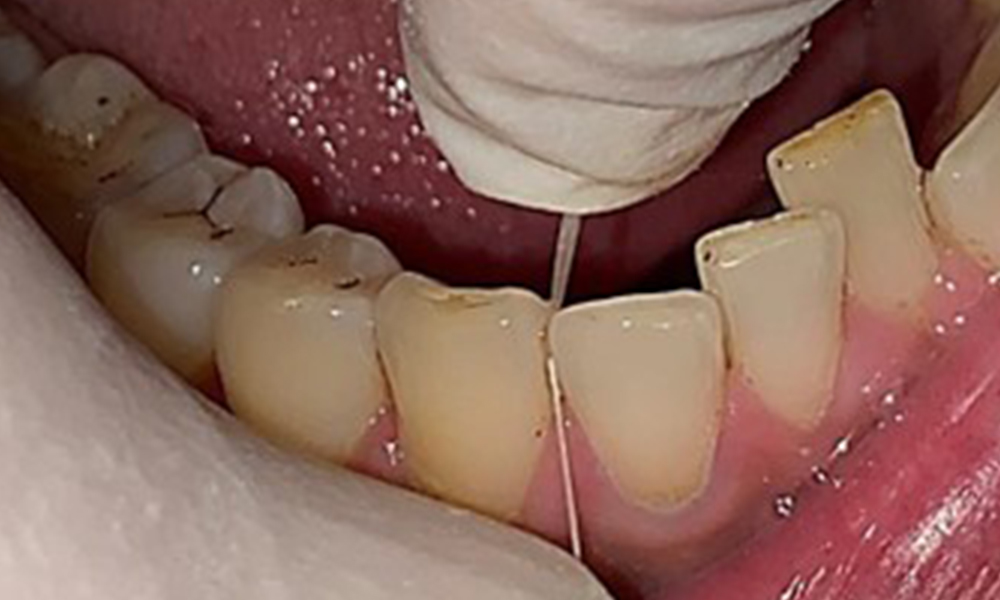

Дентални резултати

Пациентът има пълно съзъбие с общо 28 зъба. Налице са забележими ерозии и атриции. (Фиг. 4, Фиг. 5). Поради бруксизъм пациентът е носил шина с коригиран блок на захапката през нощта в продължение на много години. Ерозиите са причинени от продължителна консумация на изотонични напитки. Не сe наблюдава загуба на пародонтална кост или активни кариозни лезии.